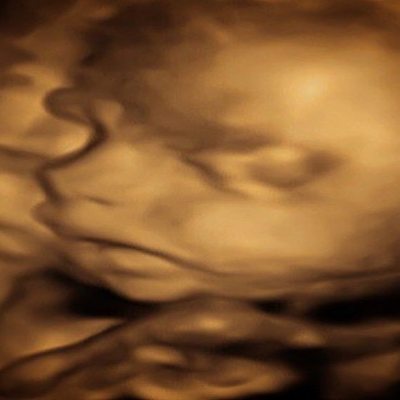

The Duke and Duchess of Sussex have announced they are expecting a baby in the Spring, but they aren't the only ones with baby news.